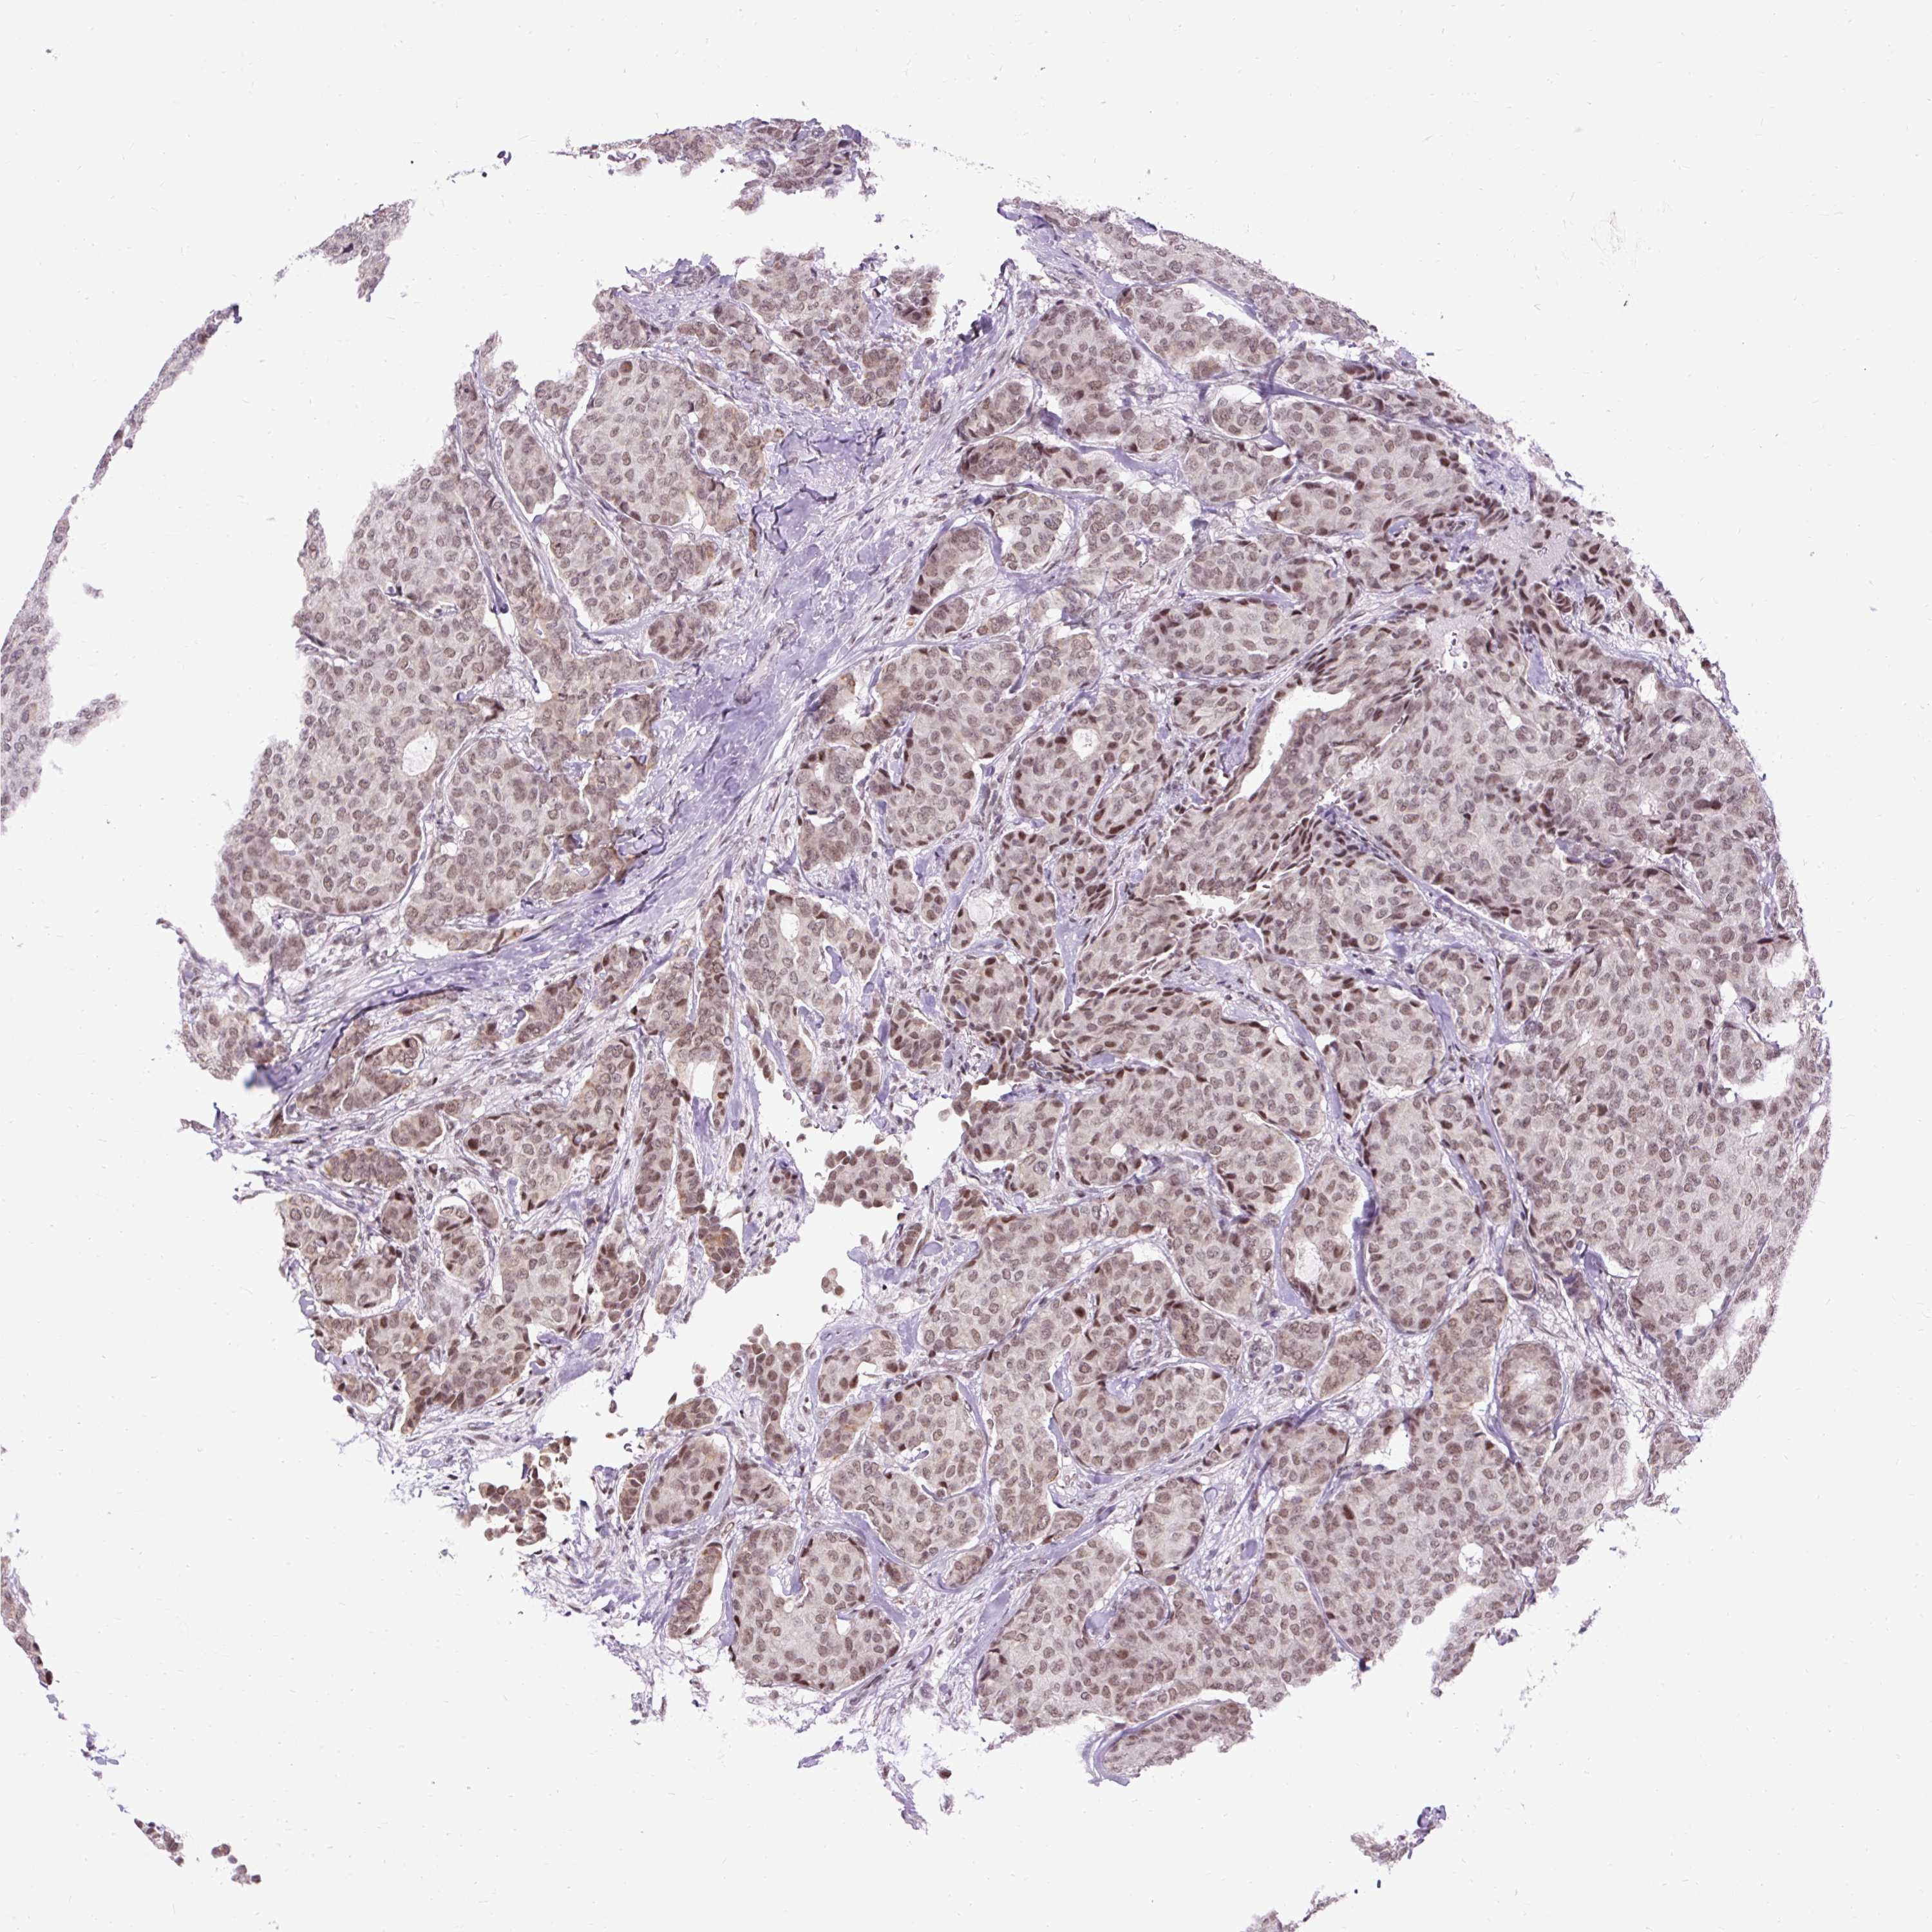

CANCER BREAST CANCER Show tissue menu

BRCA TCGA BRCA VALIDATION PROTEIN EXPRESSION